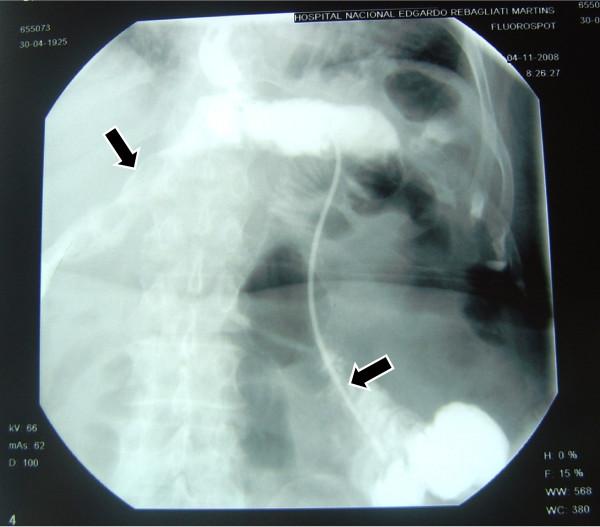

Between January 2004 to December 2008, 588 consecutive patients with a proven diagnosis of gastric cancer were taken to the operation room to try a curative treatment. Of these, 173 underwent total gastrectomy, 9 of them had esophagojejunal fistula (5.2%). In three selected patients a trans-anastomotic naso-enteral feeding tube was placed under fluoroscopic vision when the fistula was clinically detected and a complete polymeric enteral formula was used.

The complete closing of the esophagojejunal fistula was obtained in day 8, 14 and 25 respectively.